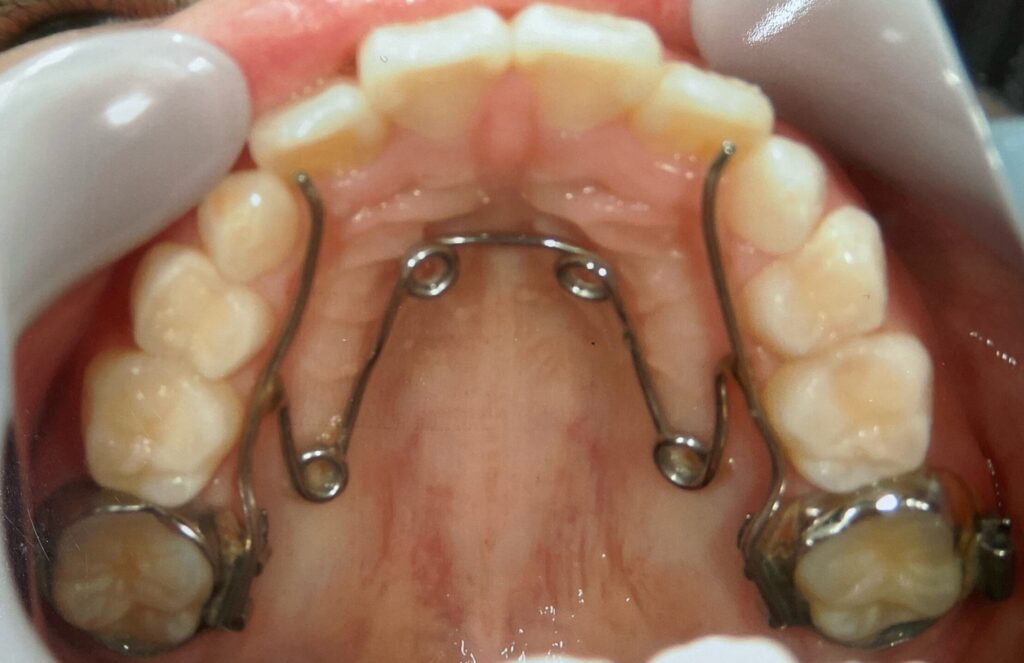

・クワッドヘリックス(顎の拡大装置)

・舌側弧線装置